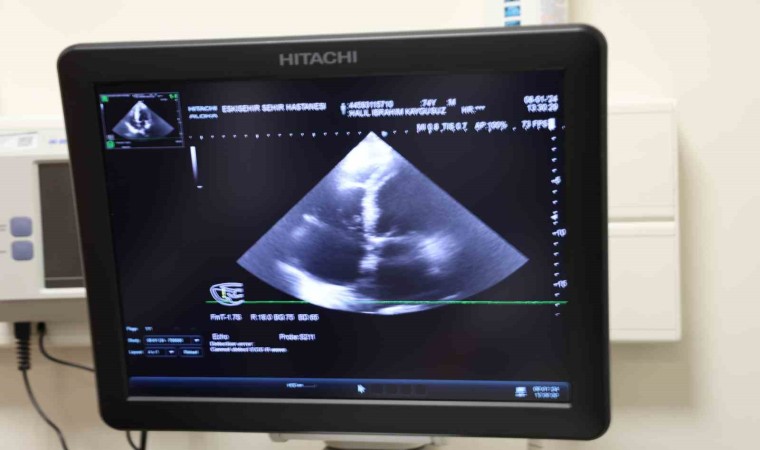

Yaklaşık 50 yıldır kalp rahatsızlığı yaşayan ve 2 kez kalpten beyne pıhtı atması sonucu felç geçiren 84 yaşındaki Yılmaz Ünallı, Eskişehir Şehir Hastanesi’nde gerçekleştirilen 30 dakikalık operasyon ile sağlığına kavuştu. Uzun yıllar ilaç tedavisi gören fakat felç rahatsızlıklarının önüne geçemeyen Ünallı, Eskişehir Şehir Hastanesi Kardiyoloji Bölümü’nde görevli Doç. Dr. Özge Turgay Yıldırım, Doç. Dr. Mehmet Özgeyik tarafından Prof. Dr. Başar Candemir desteğiyle hayatını değiştirecek bir operasyona alındı. Genel olarak açık kalp ameliyatı şeklinde gerçekleştirilebilen operasyonu, hastanın kasık bölgesinden iğneyle girerek kalbinde pıhtı atan keseciğe şemsiye şeklinde parça yerleştirilmesiyle 30 dakika gibi kısa bir sürede tamamlayan Eskişehir Şehir Hastanesi doktorları, felç rahatsızlığının tekrarlanma ihtimalini en aza indirerek 84 yaşındaki Yılmaz Ünallı’yı sürekli ilaç kullanımından kurtardı. Yapılan operasyon hakkında bilgi veren Kardiyoloji Uzmanı Doç. Dr. Özge Turgay Yıldırım, “Kasıktan anjiyo gibi plastik bir iğne üzerinden ilerleyerek sol kulakçığın içine girip, oradaki keseciği bir şemsiye benzeri malzemeyle kapattık” dedi.

Birçok hastanede açık kalp ameliyatına alınan hastaların 2 ila 4 saat kadar operasyon geçirdiğini, fakat Eskişehir Şehir Hastanesi’nde bu sol atriyal apendiks kapama işlemini kesi olmadan 30 dakikalık müdahale ile tedavi ettiklerini belirten Kardiyoloji Uzmanı Doçent Dr. Özge Turgay Yıldırım, “Biz bu işlemde ritim bozukluğu olan yüksek riskli bazı hastalarda yapılan bir işlemi gerçekleştirdik. Bu işlem bölgemizde çok sık yapılan bir işlem değildir. Biz bu hastamıza ‘Sol Atriyal Apendiks Kapatma’ işlemi yaptık, tekrarlayan inmeleri olan ve mağduriyet yaşayan bir hastamızdı. Kan sulandırıcı tedavisini almasına rağmen inme tekrarlıyordu, bu yüzden bu işlemi yapmaya karar verdik. Hastamızda ritim bozukluğu var. Bu ritim bozukluğu kalbin içindeki kulakçıkta ‘apendiks’ dediğimiz bir kesecik içinde pıhtı birikmesine neden olan bir hastalık ve kalp kaynaklı inmeye neden oluyor. Biz bu kese ağzını bir şemsiye yardımıyla kapatabilirsek, bu bölgeden pıhtı atmasını ve felç geçirmesini engellemiş oluyoruz. Normalde bu işlem açık kalp ameliyatı ile de yapılabiliyor ama bizim farklı olarak yaptığımız kasıktan anjiyo gibi plastik bir iğneyle girerek ve buradan ilerleyerek, sol kulakçığın içine girip, oradaki keseciği bir şemsiye benzeri malzemeyle kapattık. Yani herhangi bir kesi olmadan kasıktan iğne yardımıyla bu işlemi yapmış olduk ve hastamızın tekrar kalp kaynaklı inme riskini çok ciddi derecede azaltmış olduk. Bu ameliyatı açık kalp ameliyatı şeklinde yaparsak önce kemiği açmamız ve kalbin içerisine girmemiz gerekiyor. Hatta kalbi kesmemiz daha sonraysa orayı kapatmamız ve bağlamamız gerekiyor ama biz bu işlemi iğneyle kasığı uyuşturarak yapıyoruz. Bu işlem yaklaşık 15 ila 30 dakika arasında sürüyor. Hastamız ise günübirlik bir yatış sonrası taburcu olabiliyor. Eğer açık kalp ameliyatı şeklinde yapılırsa hastamızın en az bir hafta yatması gerekir, onun haricinde işlem 2 - 4 saat arası sürebilir, ameliyatın içerik ve tipine göre değişir. Gerçekten pıhtı kalp içinde bu kesecikten kaynaklıysa biz zaten bu kesenin ağzını kapatıyoruz, bu durumda bu pıhtının buradan çıkıp gitmesi teorik olarak çok zor. Çok nadir olarak tekrarlayabilir tabi ama bu hastalar normalde ömür boyu kan sulandırıcı tedaviye mahkum hastalardır, biz burayı kapattığımızda kan sulandırıcıları dahi kesebiliyoruz. En önemli artısı bu ve hastamız tekrar inme geçirmiyor. Hastamız bu işlemden sonra şikayetlerinin gerilediğini, tekrar baş dönmesi ve dengesizlik şikayetlerinin olmadığını söyledi. Klinik olarak da fayda gördük” dedi.